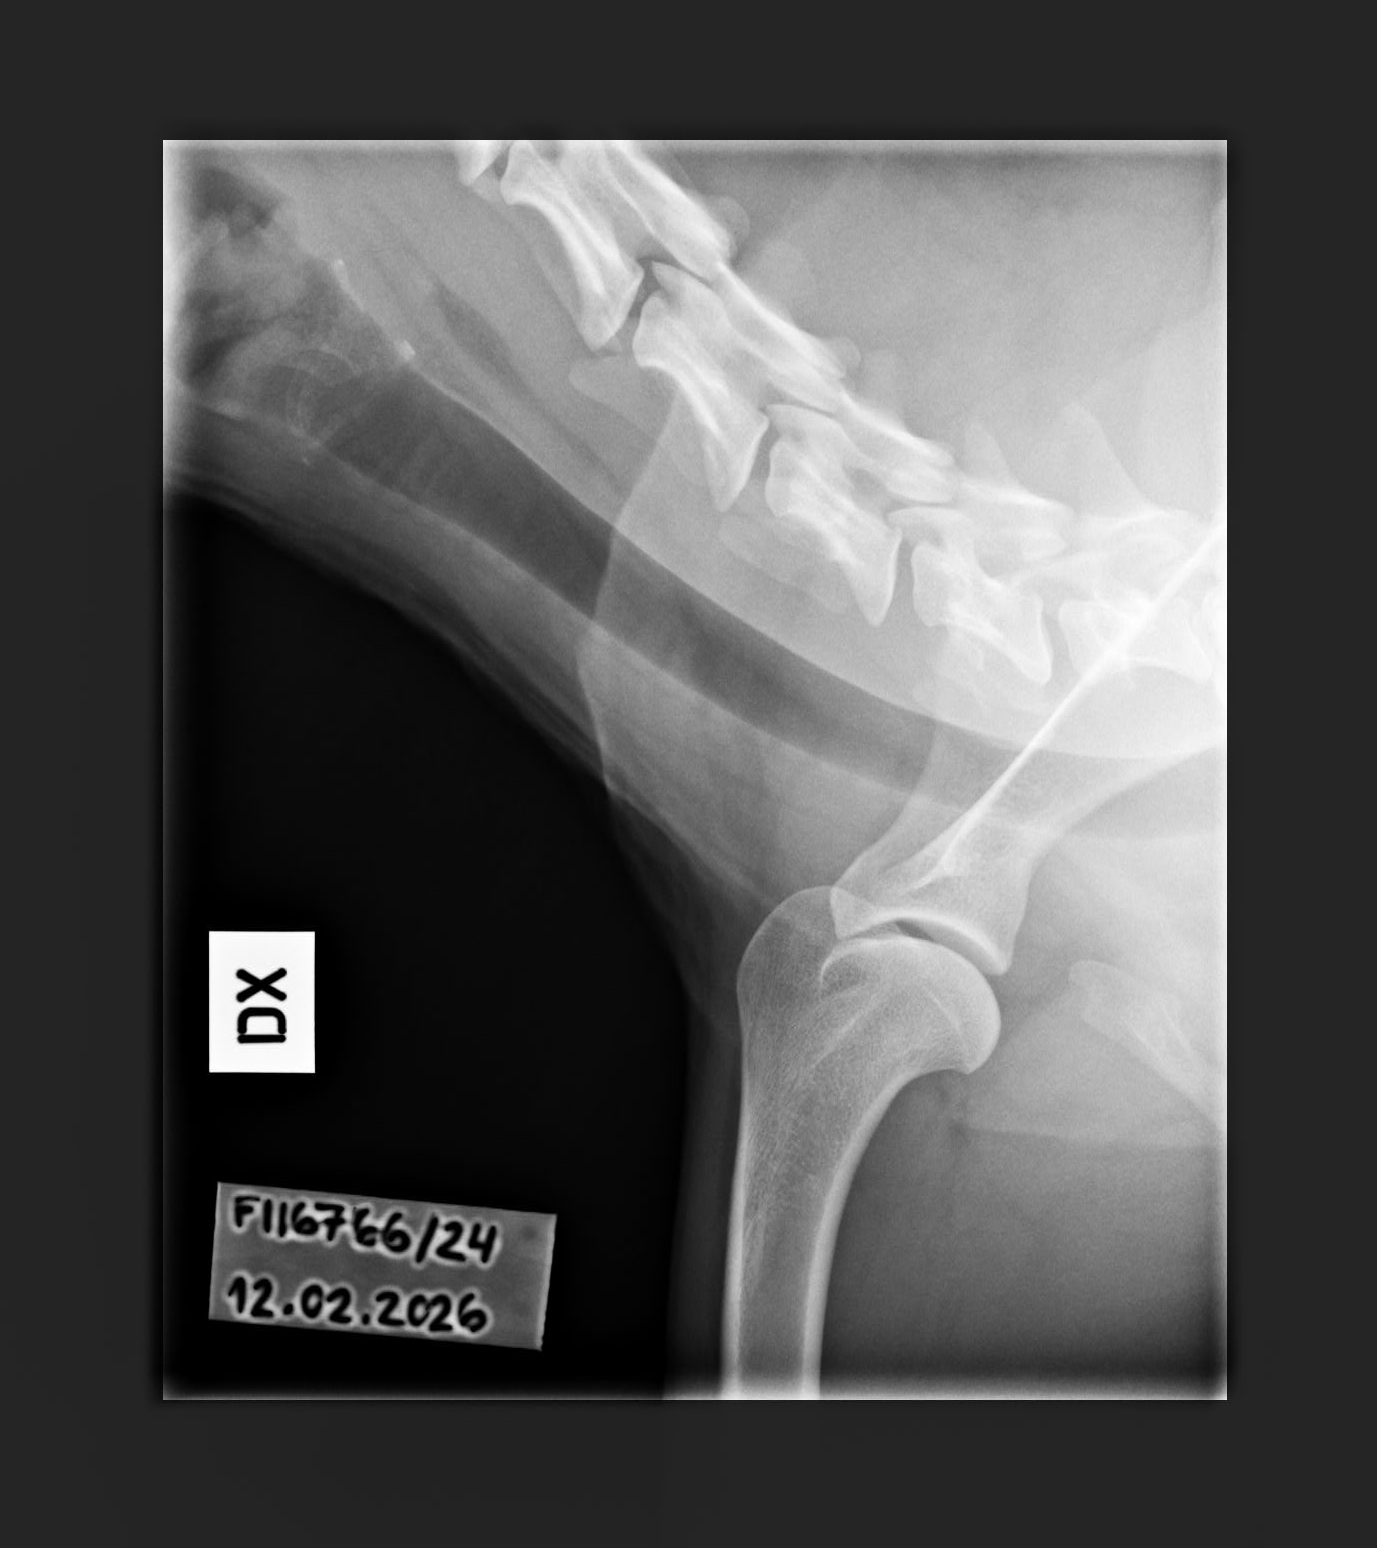

- Finnish Kennel Club's elbow x-ray report Dec '25: Signs suggestive of medial coronoid disease; further information about the condition of the joints can be obtained, if necessary, by computed tomography (CT) examination

- Finnish Kennel Club's elbow CT report Feb '26: A small amount of new bone formation around the medial coronoid process of the left elbow

- Shoulder osteochondritis: Unaffected/Unaffected